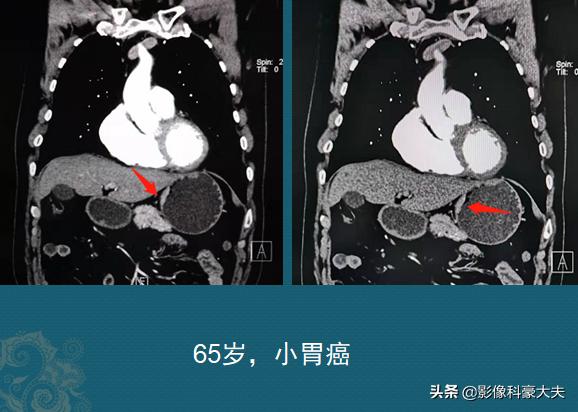

第2位老人65,也是胃疼1个月,发现大便发黑过来做胃镜,很幸运,肿瘤很小,病理是腺癌,没有周围侵犯和远处转移,两人准备同一天做手术:

这两位老人症状差不多,发病时间也都是1个月左右,但后面这位老人手术效果应该会更好一些!这也体现了癌症病人的个体差异,或者说是运气的差异……